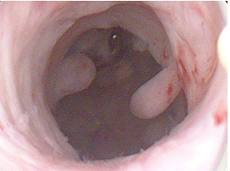

Η ασθενής τοποθετείται σε θέση λιθοτομίας και υπό γενική ή τοπική αναισθησία εισάγεται το υστεροσκόπιο διαμέσου του τραχήλου στην ενδομήτρια κοιλότητα. Γίνεται διαδοχικά επισκόπηση του τραχηλικού αυλού, πανοραμική απεικόνιση της ενδομήτριας κοιλότητας, εντοπισμός των σαλπιγγικών στομίων και ενδελεχής εξέταση όλων των παθολογικών εστιών της ενδομήτριας κοιλότητας.

Διακρίνουμε τη διαγνωστική υστεροσκόπηση και την επεμβατική, στην οποία χρησιμοποιείται το υστεροσκόπιο μεγαλύτερης διαμέτρου και μπορούν να εκτελεστούν μικροεπεμβάσεις με τη βοήθεια ειδικών εργαλείων.